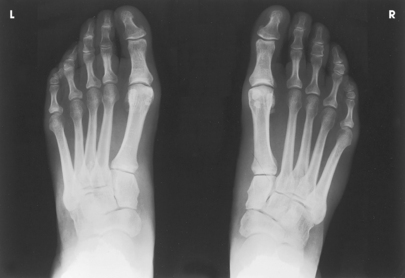

Structures shown: The resulting image shows a lateromedial projection of the bones of the foot with weight-bearing. The projection is used to show the structural status of the longitudinal arch. The right and left sides are examined for comparison (Figs. 6-55 and 6-56).

Structures shown: The resulting image shows a weight-bearing AP axial projection of both feet, permitting an accurate evaluation and comparison of the tarsals and metatarsals (Fig. 6-58).